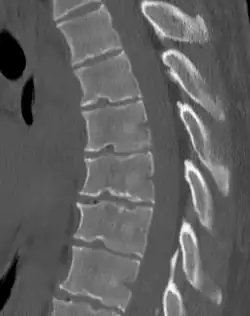

Scheuermann's disease

| Scheuermann's disease on lateral Xray of the T spine | |

Scheuermann's disease is a skeletal disorder.[3] It describes a condition where the vertebrae grow unevenly with respect to the sagittal plane; that is, the posterior angle is often greater than the anterior. This uneven growth results in the signature "wedging" shape of the vertebrae, causing kyphosis. It is named after Danish surgeon Holger Scheuermann.[4][5][6]

Diagnosis is typically by medical imaging. The degree of kyphosis can be measured by Cobb's angle and sagittal balance.